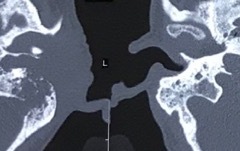

Cholesteatoma Diagrams

Cholesteatoma Clinical

Scans